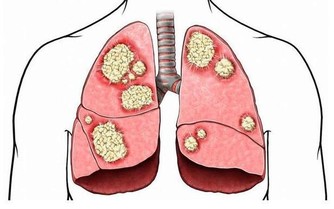

為何泡個腳就猝死 ?該醫院神經外科主任程新富介紹,經檢查發現,劉霞頭部腦血管有動脈瘤突發破裂。腦動脈瘤在未破裂前少有徵兆,很難發現,而一旦破裂,就會突發劇烈頭痛、意識障礙、噁心、嘔吐等癥狀,情況很兇險,致死、致殘率較高。少數特殊的腦血管動脈瘤會有眼瞼下垂、夜間頭痛、行走不穩等早期癥狀。